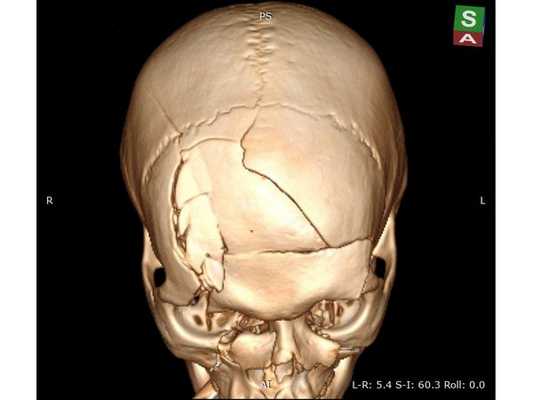

КТ головного мозга: оскольчатый вдавленный перелом лобной кости, линейный перелом ската затылочной кости, а также перелом лицевого отдела черепа III степени по Le Fort с остаточной деформацией стенок; множественные ушибы и отёк вещества головного мозга лобных долей; скопление крови в пазухах носа. КТ шейного и поясничного отделов позвоночника: травм и патологий нет. КТ грудной клетки и грудного отдела позвоночника: ушиб правого лёгкого. Офтальмологический осмотр: контузия правого глазного яблока тяжёлой степени, скопление крови между сетчаткой и пигментным эпителием левого глаза.

Сочетанная черепно-челюстно-лицевая травма. Открытая проникающая черепно-мозговая травма. Ушиб головного мозга тяжёлой степени с преимущественным поражением лобных долей и формированием очагов размозжения в полюсно-базальных отделах. Многооскольчатый вдавленный перелом лобной кости, переходящий на основание черепа. Перелом лицевого отдела черепа III степени по Le Fort с деформацией стенок правой глазницы. Ушиб правого глаза тяжёлой степени, субретинальное кровоизлияние левого глаза.